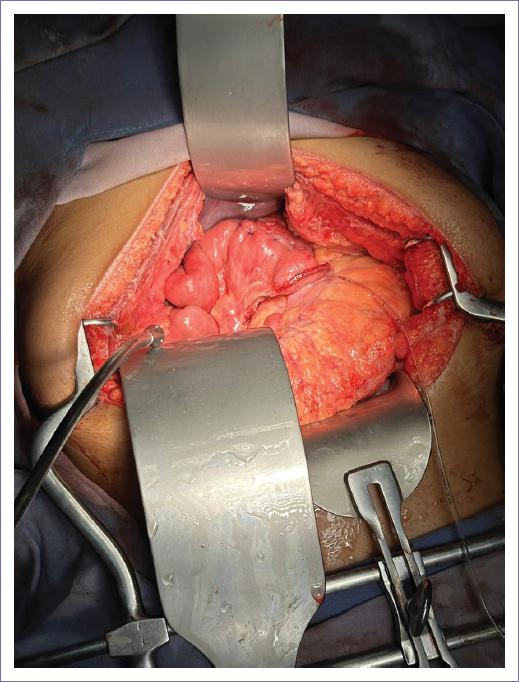

Se integró el diagnóstico de un tumor sólido pseudopapilar de páncreas y se programó para pancreatoduodenectomía ampliada con probable resección venosa. Previo protocolo quirúrgico completo, bajo anestesia general, se realizó incisión en línea media supraumbilical e infraumbilical, se realizó disección hasta cavidad, encontrando tumor sólido en la cabeza que abarcó hasta el cuerpo de páncreas de 12 x 15 cm (Fig. 2). Se realizó abordaje mesentérico, se continuó la liberación y disección de vasos cólicos derecho y medios, se cortó y ligó tronco gastrocólico de Henle, se liberó cuerpo de la vena esplénica, se realizó disección del hilio hepático con linfadenectomía, se realizó disección del conducto hepático común, disección portal, se cortó y ligó arteria gastroduodenal, se liberó ligamento de Treitz, se realizó corte yeyunal 10 cm distales, se ligó y cortó ramas mesentéricas, se trasladó yeyuno al lado derecho de los vasos mesentéricos, se cortó antro gástrico con engrapadora lineal cortante; previa ligadura de arteria gástrica derecha, se realizó corte de conducto hepático común, se realizaron suturas transfictivas a nivel del cuerpo de páncreas, con un margen de 1 cm distal al tumor, se realizó corte y extracción de la pieza. Se procedió con la fase reconstructiva con pancreatoyeyunoanastomosis terminal lateral con técnica de Blumgart con colocación de un tutor externo (Fig. 3), hepatoyeyunoanastomosis a 10 cm término-lateral (Fig. 4), gastroyeyunoanastomosis término-lateral a 50 cm hepático-yeyuno con engrapadora lineal cortante 55 mm (Fig. 5). Se lavó la cavidad, se procedió a cierre por planos y se colocaron drenajes.